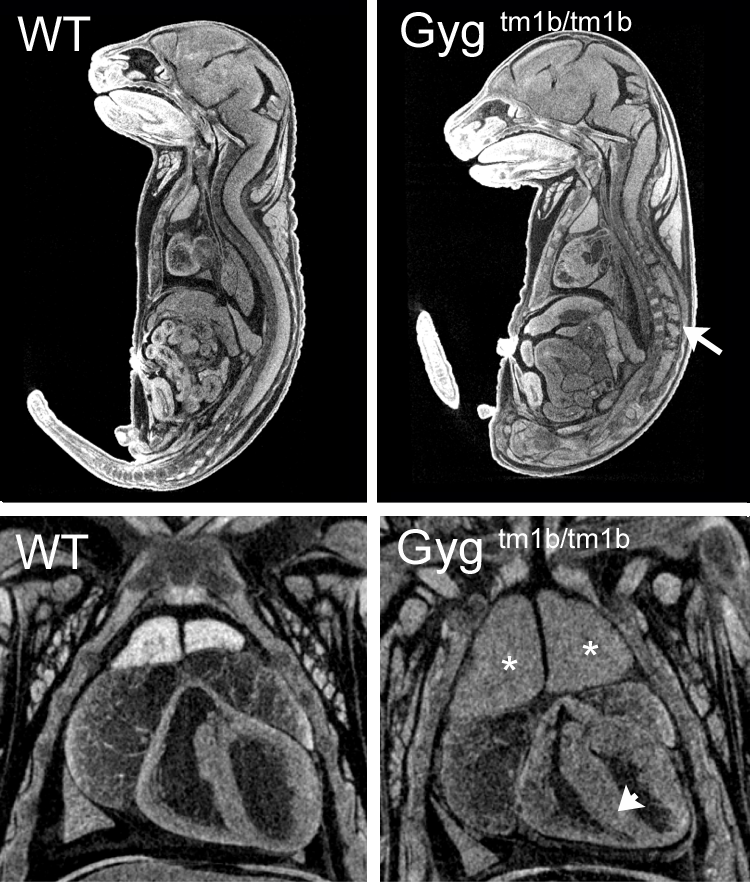

Glycogenin is an enzyme that converts glucose to glycogen. Glycogenin catalyzes UDP-alpha-D-glucose + glycogenin ⇌ UDP + alpha-D-glucosylglycogenin. The enzyme is a homodimer of 37 kDa subunits. Mutations in human GYG1 are associated with Glyocgen Storage Disease XV and Polyglucosan Body Myopathy 2 (OMIM). Homozygous null Gyg mice die between birth and weaning but were found in normal proportions at E18.5. Mutants were indistinguishable from littermates at E12.5, E15.5 or E18.5 but analysis of microCT images revealed obvious cardiac abnormalities, enlarged thymus and abnormal nervous system morphology. This is the first reported Gyg mouse mutant.

Single images from E18.5 microCT volumes showing spinal cord abnormalities (arrow), enlarged thymus (asterisk) and thickened myocardium (arrowhead) in homozygous null embryos compared to wild-type littermates.